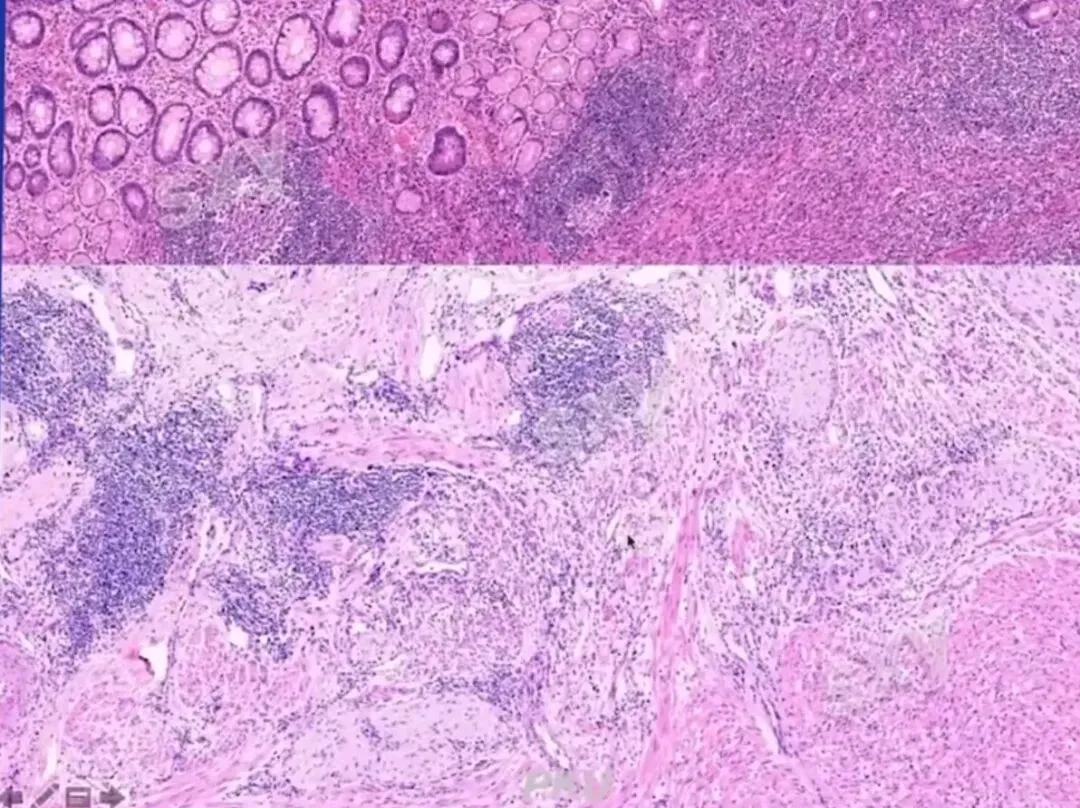

>课件分享:炎症性肠病的病理诊断

课件分享:炎症性肠病的病理诊断